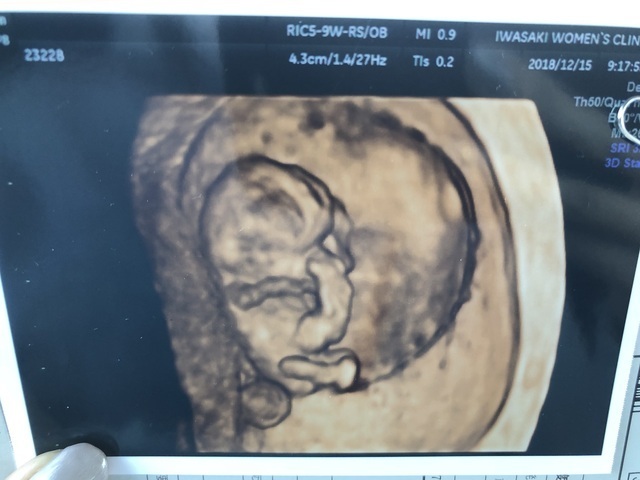

9週0日(9w0d・性別不明・双子)|みーやま さん(27歳)

エコー写真撮影時のエピソード:

なかなか授からず、3年目にして授かり毎回検診でちゃんと育っているか不安でした。この9wの時、双子が発覚!!驚きとうれしさと不安にもなりました。

けど、旦那も親も喜んでくれて、今まで不妊治療を頑張ってきて本当に良かったと思いました。つわりも妊娠後期も体調がよくなく、管理入院になりましたが、無事元気に生まれてくれて、今本当に幸せです。